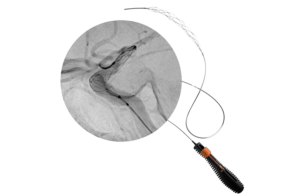

Rapid Medical announced today that it received FDA clearance for the Tigertriever 25 thrombectomy device, its latest addition to the platform.

Designed specifically for large clot burden in proximal vessels, Tigertriever 25 combines a 53 mm capture length with proprietary real-time force control. This enables physicians to actively control clot interaction during procedures. The company said this produces consistent performance across a range of clinical scenarios, including long thrombi and stenotic vessels.